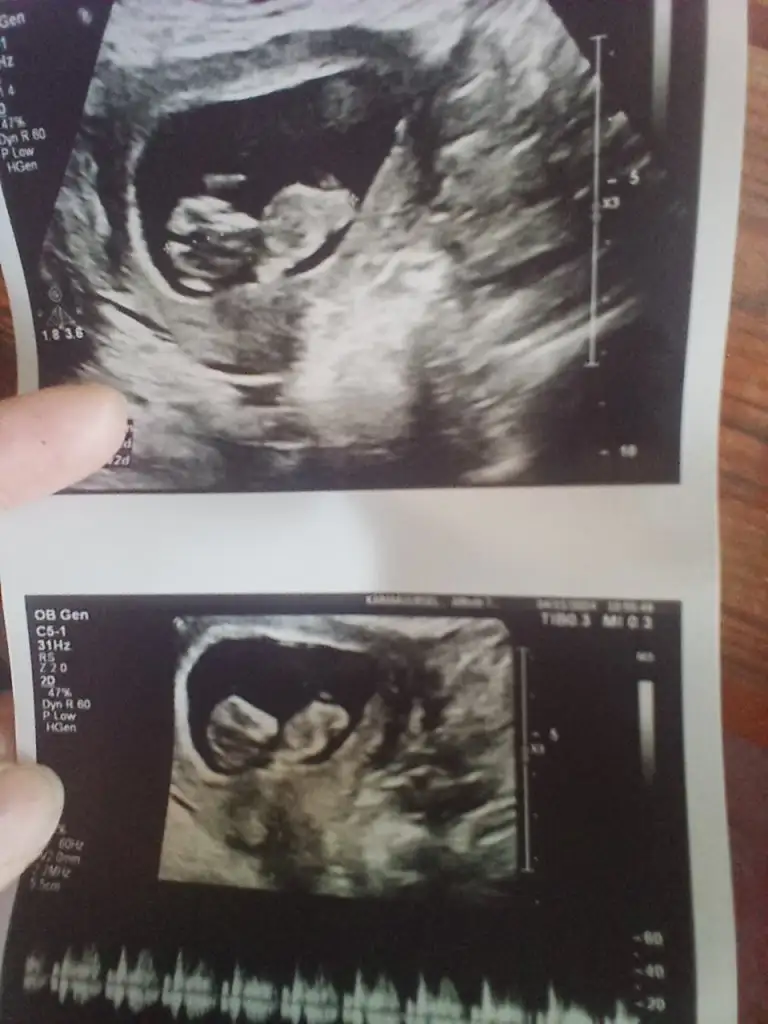

Benim bebişime de bakar mısınız 20 haftalık olacak neredeyse ama önce erkek sonra kıza döndü